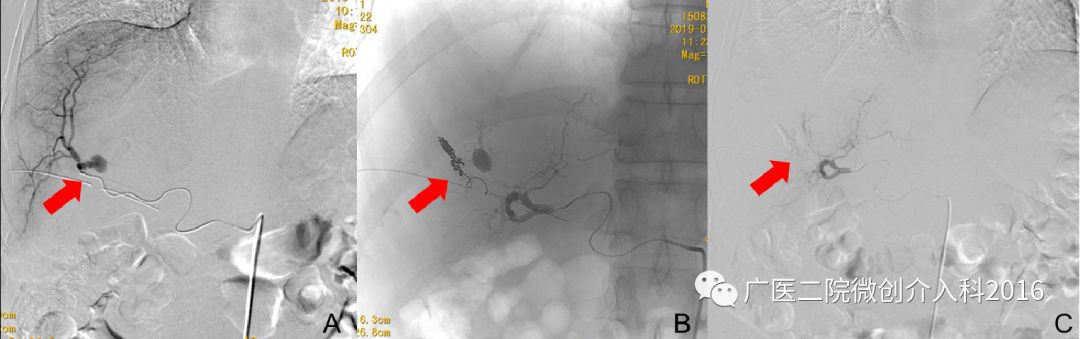

患者为经皮胆道取石术后胆道出血,经内科药物治疗无效,仍有大量出血。图A行肝动脉造影,右肝可见造影剂外溢并呈囊状扩张,表示正在出血。图B行介入栓塞治疗,注入不同规格的弹簧圈行出血动脉栓塞术。图C再次造影可见原出血征象消失,患者胆道出血停止。